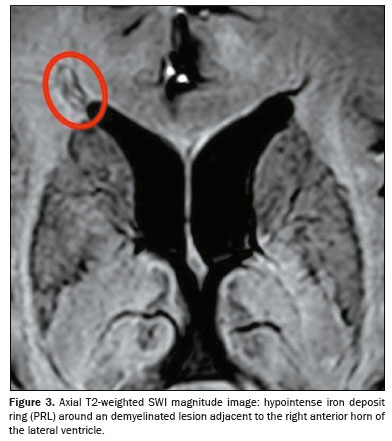

Representative lesions, including one with a CVS, are illustrated in Figures 2 and 3. As shown in Table 2, Figure 4, and Figure 5, the proportion of CVS-positive lesions was higher in the MS group than in the migraine group (61.8% vs. 10.4%).

All of the patients in the MS group had at least one PRL, whereas no PRLs were identified in the migraine and control groups. Of the 1,697 lesions identified in the MS group, 605 (35.7%) were PRLs, with a median per patient of 13.5 PRLs. Figures 2 and 3 show distinctive examples of PRLs, and Figure 6 shows the distribution of PRL locations across the groups.